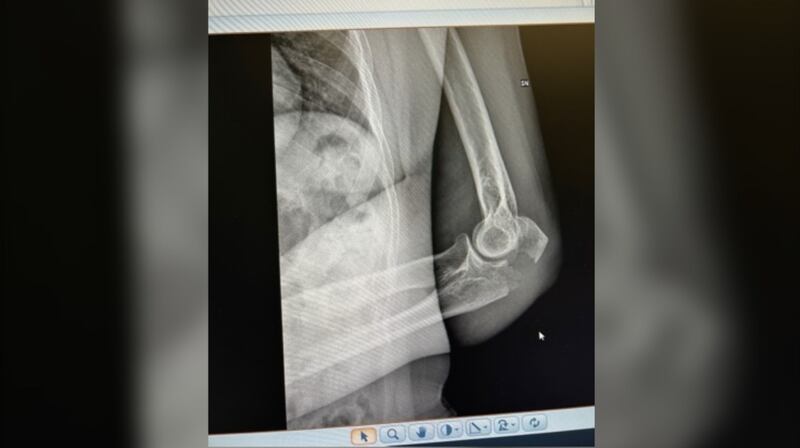

Au total, elle a subi une fracture «grave» de l’épaule gauche, trois côtes cassées, une cheville cassée et trois orteils cassés. Les médecins lui ont dit qu’elle avait besoin de plaques en métal pour réparer son épaule brisée.

Quand elle est arrivée à l’hôpital à San Gimignano, une ville médiévale perchée sur une colline dans la pittoresque région de Toscane en Italie, le médecin lui a mis une attelle au coude et lui a proposé de faire la chirurgie nécessaire dans deux ou trois jours.